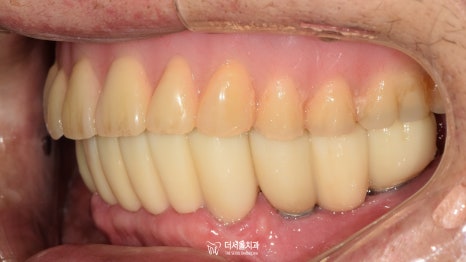

며칠 뒤, 크라운 세팅을 위해 다시 오셨습니다.

예쁘게 제작된 보철을 올려드리며

사후관리까지 약속드린 후에 마무리를 했습니다!

불편한 틀니를 교체하기 위해

하악 네비게이션 임플란트 를 진행했던 증례였습니다.

그러나 여기서 한 가지 알아둬야 될 게 있죠.

틀니의 힘이 10이라면

내 치아의 힘은 100

네비게이션 임플란트 의 힘은 1000입니다.

튼튼하고 예쁜 이가 생겼다고

너무 무리하게 사용을 하게 되면

틀니가 와장창 깨지거나 부러질 수 있기 때문에

이렇게 대합 되는 보철의 종류가 다른 경우에는

좀 더 주의 깊은 사용이 필요합니다.